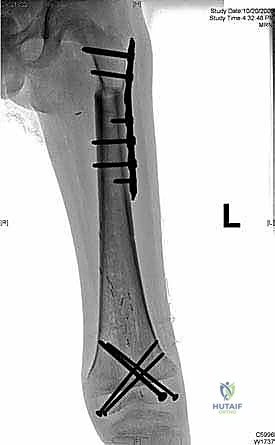

We also decide on the type and length of fixation. Plate fixation allows for standard osteosynthesis techniques and compression across the allograft-host junctions, which we believe improves healing. However, the screw holes created in the allograft are a recognized risk factor for late allograft fracture. Alternatively, intramedullary (IM) nail fixation, while potentially requiring additional incisions, generally provides stronger, more protective long-term fixation for the allograft without creating stress risers from screw holes. The challenge with IM fixation can be achieving compression at the host-graft junctions, which may impede healing. Sometimes, a combination of techniques is employed.

Here, you can see the power saw making a precise transverse osteotomy. Note the constant irrigation to prevent thermal damage to the bone.